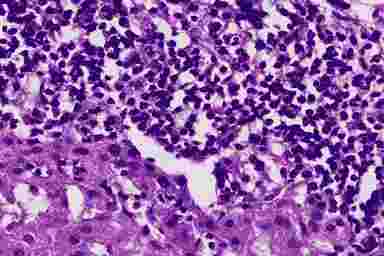

В I стадию происходит разрушение междольковых желчных протоков в зоне гранелематозного воспаления. Разрушающиеся желчные протоки в виде муфт окружены клетками воспалительного инфильтрата, преимущественно лимфоцитами, портальные тракты густо инфильтрированы лимфоцитами, плазмоцитами, макрофагами, в небольшом количестве эозинофилами (рис. 14.2).

Первичный билиардный цирроз печени

Рис. 14.2. Первичный билиардный цирроз печени (биоптат печени, окраска г/э, х400). Деструктивный холангит. Рядом с протоком - гранулема, лимфоидный инфильтрат